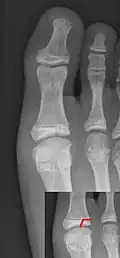

Salter–Harris III fracture of big toe proximal phalanx. -

Salter–Harris IV fracture of big toe proximal phalanx.